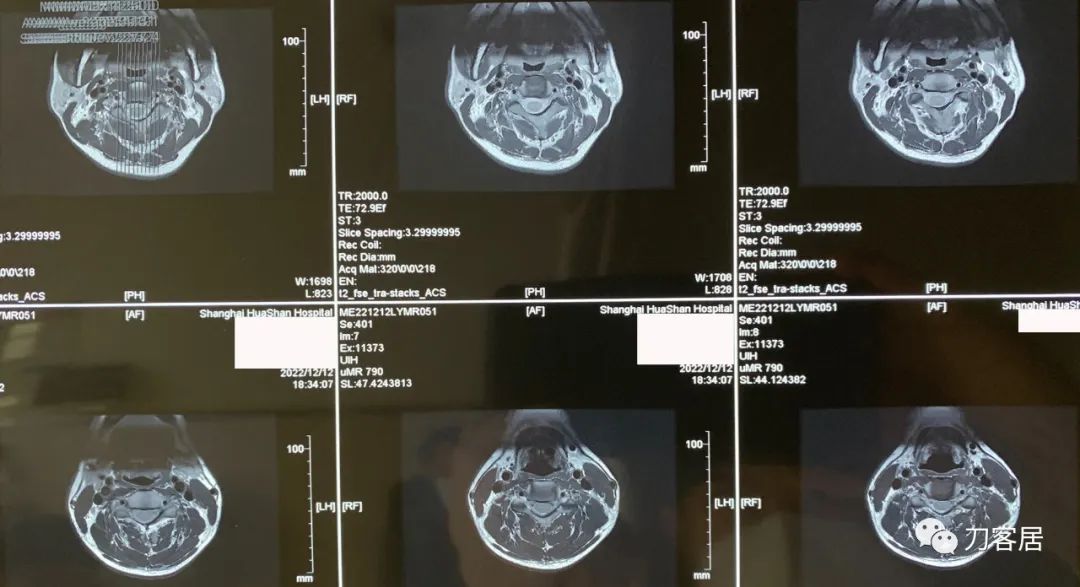

图4. 20221212上海华山医院颈椎MRI04,此平面横截面显示,椎管容积尚可。

图5. 20221212上海华山医院颈椎MRI05,此平面横截面显示,椎管容积尚可。